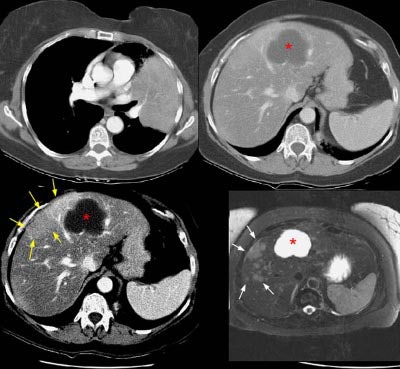

The patient below had an adenocarcinoma in the left lung that was obstructing the left upper lobe bronchus (left image upper row). The staging CT scan demonstrated a large liver cyst (*) and some underlying hepatic heterogeneity best appreciated on liver windows (yellow arrows). The patient had slightly elevated liver function tests, and the findings were felt to be most likely related to areas of sparing in a patient with some hepatic fatty infiltration. Because the possibility of metastatic disease could not be excluded, an MRI of the liver was performed. The heavily T2-weighed image shown (right image bottom row) revealed multiple liver metastases, many of which were not apparent on the contrast-enhanced CT scan (white arrows). MR imaging has been shown to be more sensitive for detecting liver metastases when compared to CT.